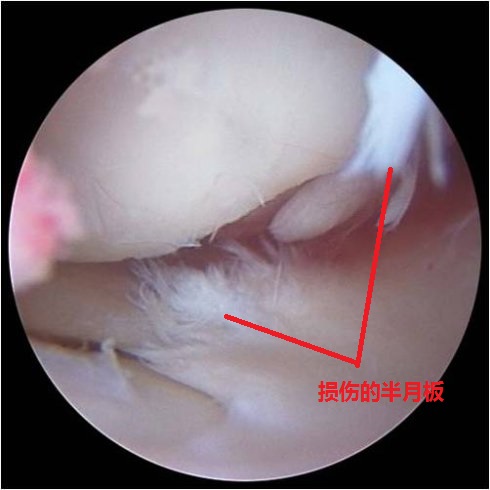

半月板是纤维软骨,名字就是根据形状来的。它可厉害了,比冰面还光滑3倍。咱们跑步时候,膝关节要承受至少3倍于体重的冲击,抵消这冲击的主要功臣之一就是半月板。稳定、缓冲、润滑、吸震,它就这么任劳任怨默默无闻的发挥着作用。为啥说默默无闻呢,因为半月板绝大部分没有血管神经,它受伤了你也不知道啊。咦,好像有哪里不对,不知道?可是我明明感觉疼啊。

看图你就明白了,半月板撕裂后的样子,是这样飘荡着的絮状物。这些“毛毛”会刺激到周围组织,比如滑膜,滑膜就会出现炎症,产生积液,进而会肿、会疼;“毛毛”还会飘到你的关节缝隙里,卡住你的关节,于是你发现腿不能弯了,一屈伸就疼。